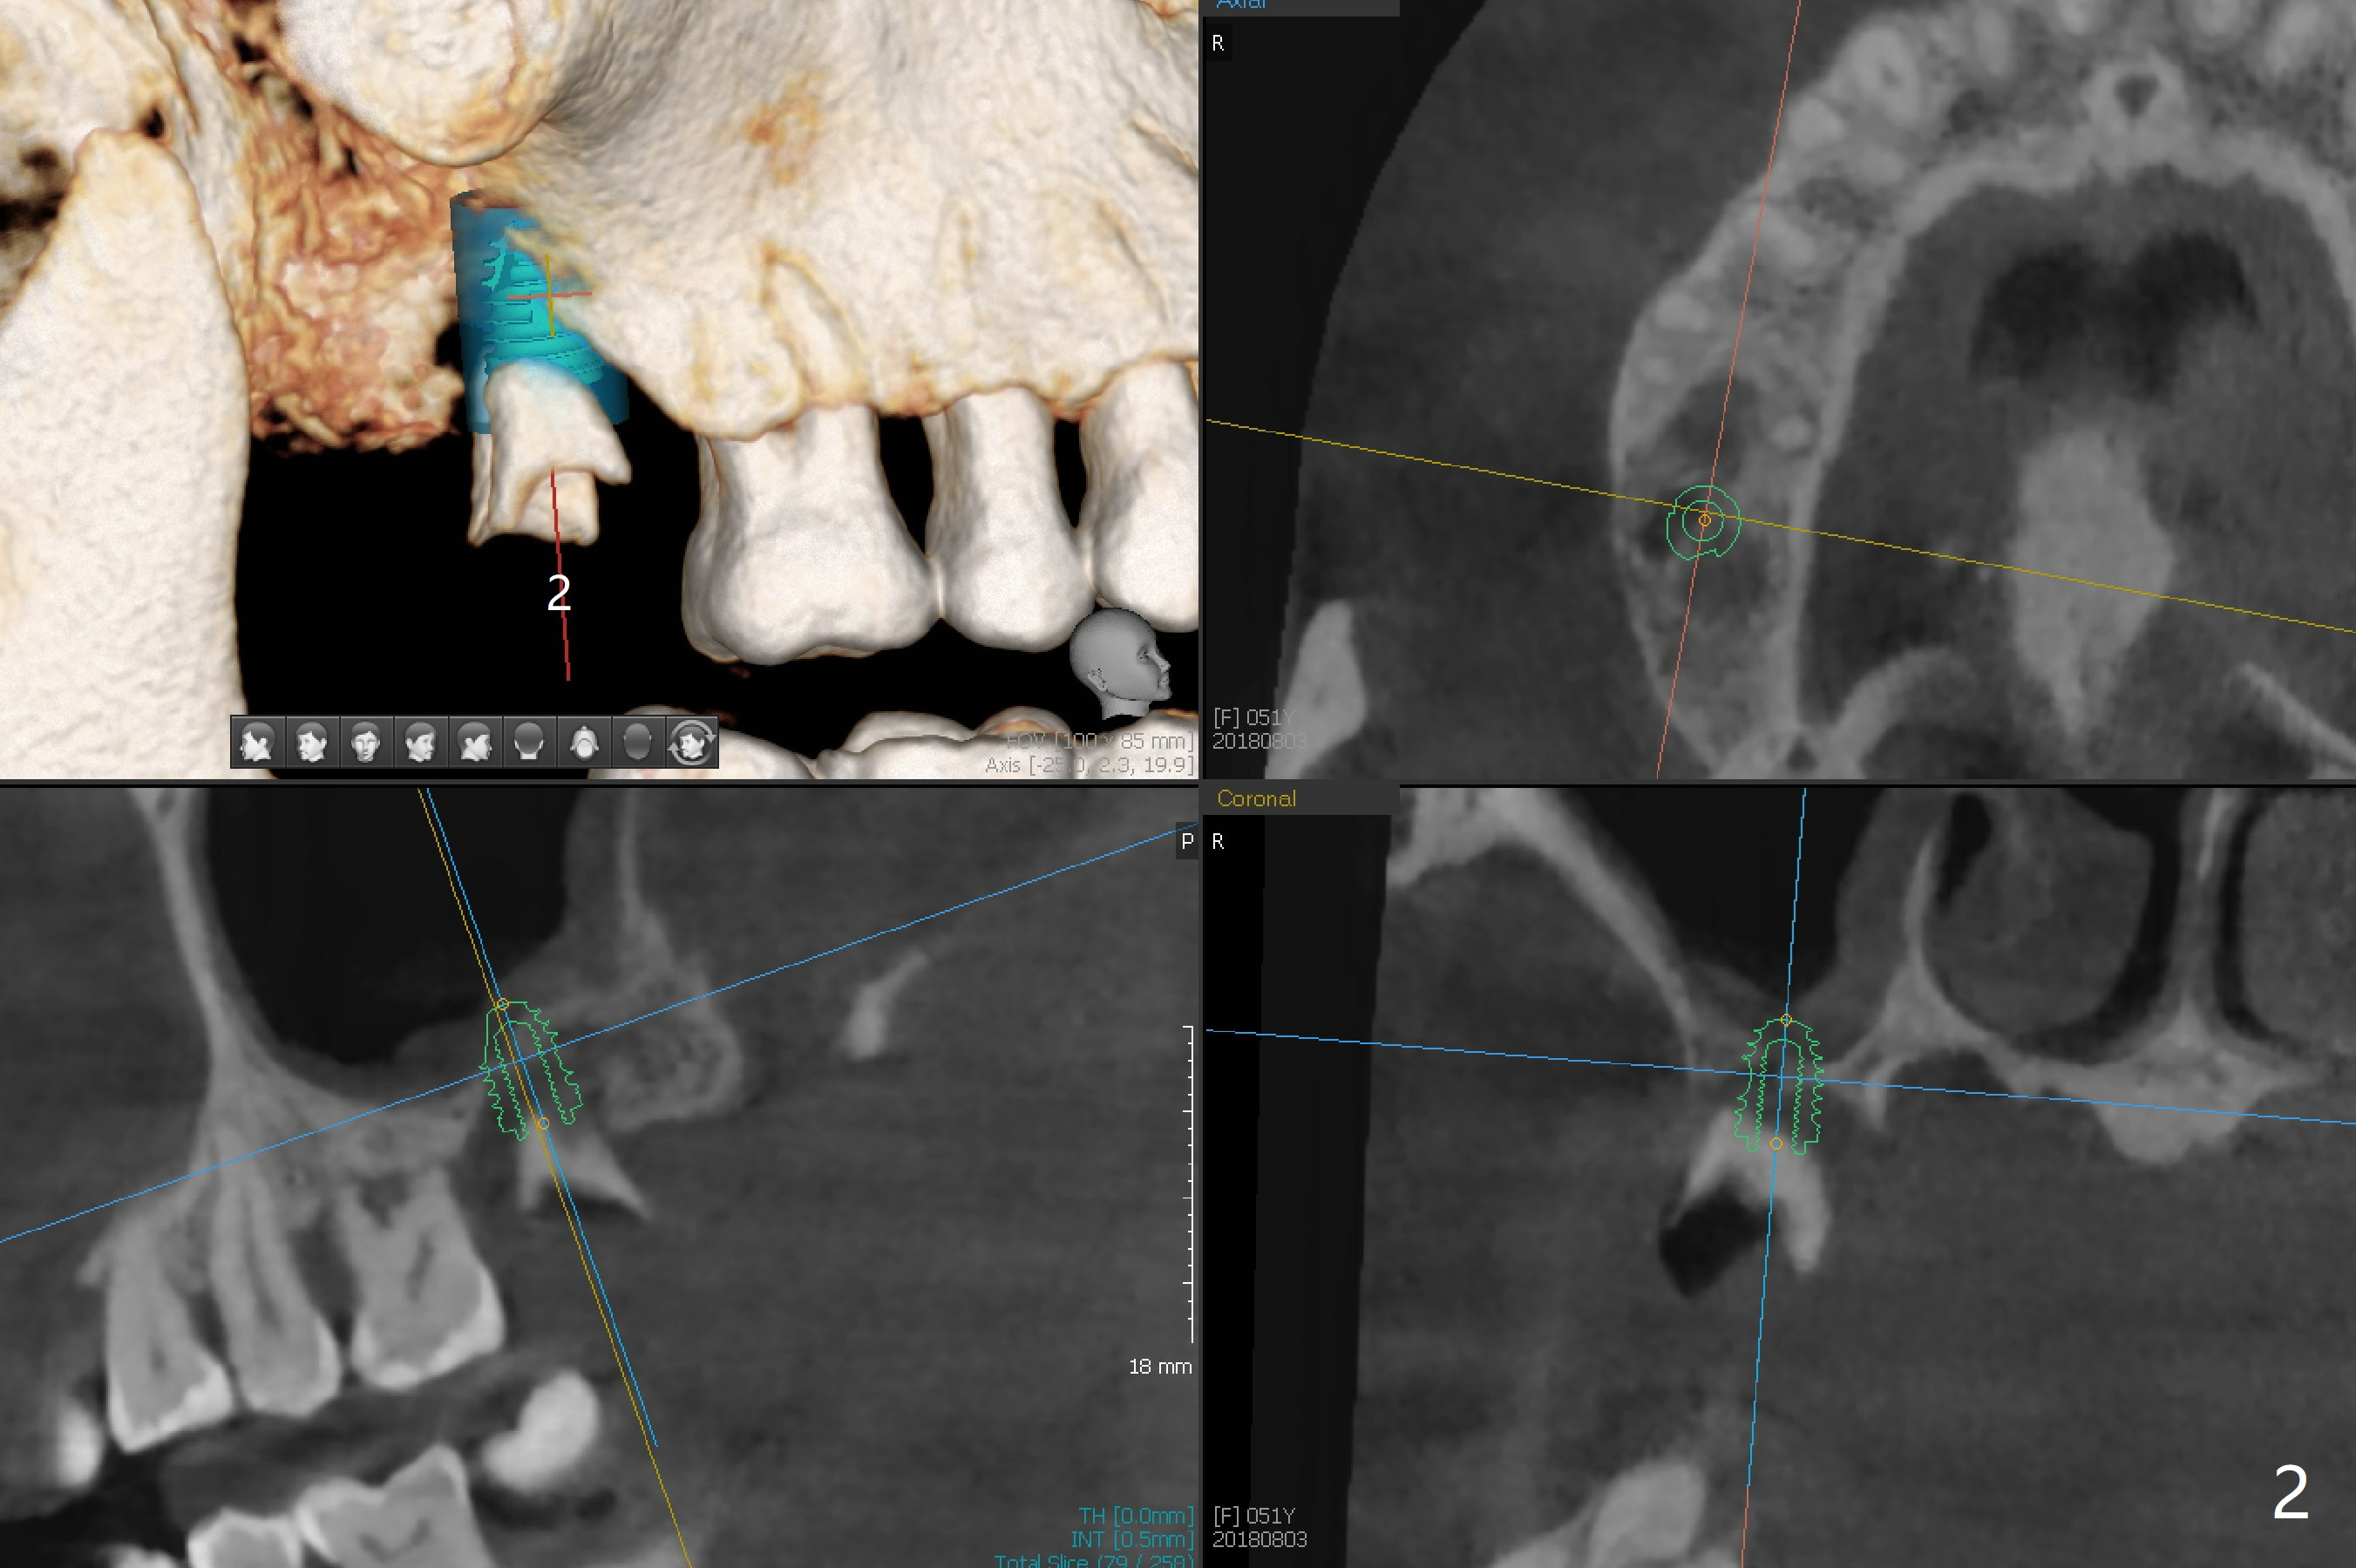

A 51-year-old woman with apparent chronic periodontitis (Fig.1) has the teeth #13 and 14 extracted with socket preservation in her home country 3 months earlier (Fig.3,4). The bone height associated with the residual roots at #2 is short; a 5x7.3 mm implant seems to be appropriate (Fig.2). Use Magic expanders and sinus lifter. The implant will be Magicore or consistent with those at #13 and 14. Prepare 2 pieces of PRF membrane for sinus lift and buccal defect. Osteotomy at #13 should be palatal (Fig.3 red line instead of blue one) to obtain more of the apical native bone for primary stability. Prescribe Augmentin after sinus lift. Osteotomy at #14 should be a little bit more distal because of the mesial shift of the tooth #15 (Fig.4). Early provisional to hold the edentulous space and limited ortho may be required. A guide will be made for #13 and 14.